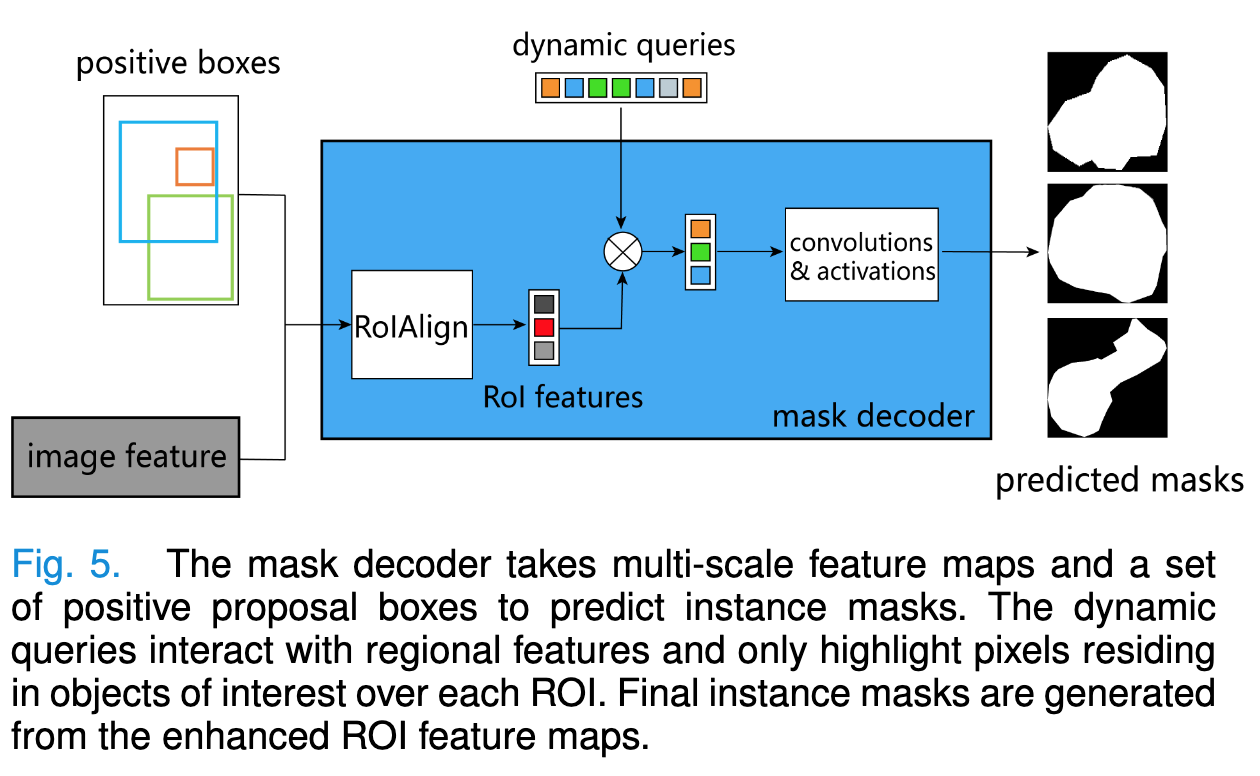

| Advances in Kidney Biopsy Structural Assessment through Dense Instance Segmentation Authors Zhan Xiong, Junling He, Pieter Valkema, Tri Q. Nguyen, Maarten Naesens, Jesper Kers, Fons J. Verbeek 肾活检是诊断肾脏疾病的金标准。肾脏病理学家专家做出的病变评分是半定量的,并且观察者之间的变异性很高。因此,自动获取每个分割的解剖对象的统计数据可以在减少劳动力和观察者之间的变异性方面带来显着的好处。然而,活检的实例分割一直是一个具有挑战性的问题,因为a平均有大约300到1000个密集接触的解剖结构,b具有至少3个的多个类,c具有不同的尺寸和形状。当前使用的实例分割模型无法以有效且通用的方式同时应对这些挑战。在本文中,我们提出了第一个无锚实例分割模型,该模型结合了扩散模型、变压器模块和 RCNN 区域卷积神经网络。我们的模型仅在一台 NVIDIA GeForce RTX 3090 GPU 上进行训练,但可以有效识别肾活检中 3 种常见解剖对象类别(即肾小球、肾小管和动脉)的 500 多个对象。我们的数据集由从 148 张琼斯银染肾全切片图像 WSI 中提取的 303 个斑块组成,其中 249 个斑块用于训练,54 个斑块用于评估。此外,无需调整或重新训练,该模型可以直接转移其域,从 PAS 染色的 WSI 中生成良好的实例分割结果。 |